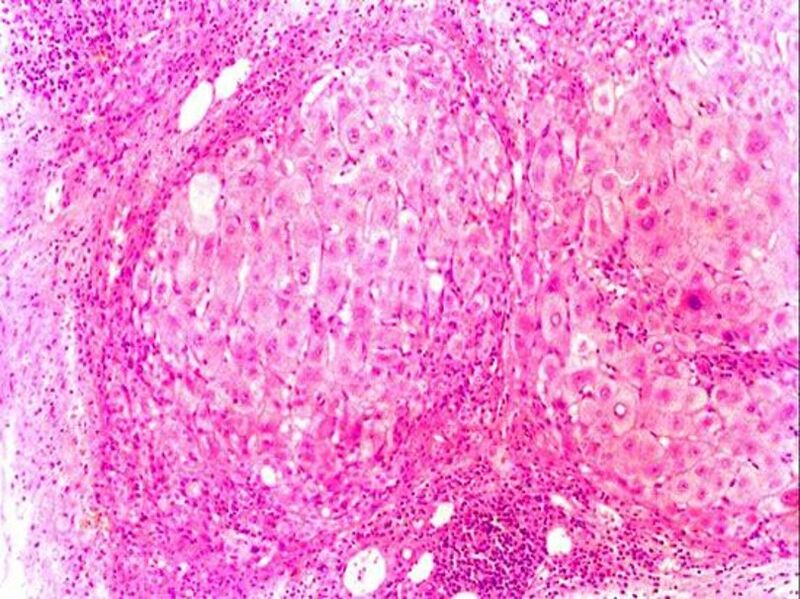

文件:28号切片-肝硬化-镜下观6-见假小叶内变性、坏死、再生的肝细胞.jpg

原始文件(809 × 606像素,文件大小:177 KB,MIME类型:image/jpeg